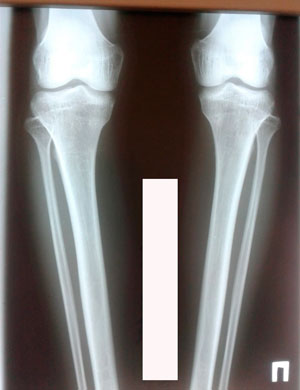

Дата операции 28.01.2020

Дата снятия аппаратов - 26.05.2020

Вложения

image-26-05-20-12-43-1.jpg

image-26-05-20-12-43.jpg